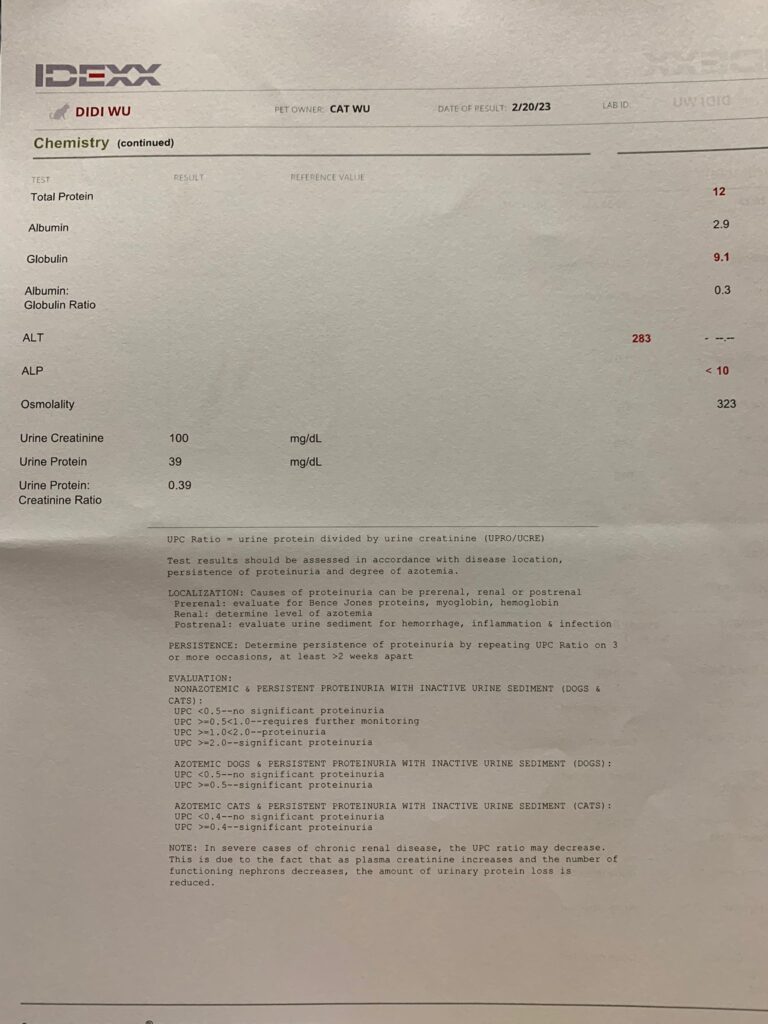

Noon: dr d “Polyclonal for didi, so no clear tumor suspect. This happens in chronic inflammation, either viral bacterial or parasitic. Or immune mediated. but very unlikely the tumor we thought…. myeloma would not look like this. so can almost 95% rule out. or try investigate lot further, maybe try to get sample from the enlarged liver or lymf nodes. lot more invasive. have you given him an antibiotic trial at some point already? dewormer?” – reminded dr d that didi alr on Clav jab 0.19ml

Glob wbc producing tumor – send out to see the diff type of glob results. If one type of glob go up, then highly is tumor. If all go up then not as bad.

Rbc down to 6.12, lucky HCT still 30.3%.

Wbc NEU all go up.

45mg once daily ursofalk for the gall bladder too.

Alt 283- given milk thristle he really hate it. I suddenly think of ornipural – I think first.

Cbc looks fine. Omg the price of Cbc so ex here. NEU EOS high, I’m happy actually – better than Low. Thought is like xiao Hui false alarm, can survive de!!! TP 10.5, glob 7.5. dr d didn’t mention he needs any ab at all.